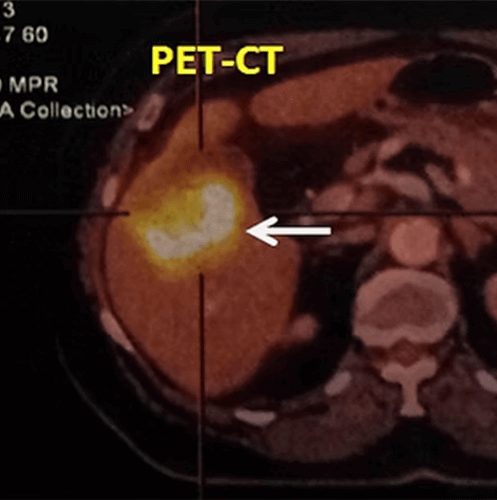

Another method increasingly used recently in breast imaging is MRI (Magnetic resonance imaging). MRI does not use radiation, but it is more expensive and time-consuming. It is the most sensitive method (around 95%) to show the masses in the breast. Therefore, if a patient suspected of having a breast mass, has a normal MRI, the likelihood of breast cancer is largely ruled out. However, MRI also show benign masses more frequently than ultrasound and mammography and may cause confusion since it is not successful enough to differentiate cancer from benign masses (the specificity is low). Therefore, it is recommended MRI be used only supplementary to ultrasound and mammography in suspected cases and in high-risk patient groups. PET-CT is not used in routine breast examinations because it uses a higher radiation dose, but it is an extremely successful method for demonstrating the extention of breast cancer.

In our patient who underwent cryoablation for breast cancer and single bone metastasis, the control PET-CT taken three months later shows that the breast tumor shrunk and its activity disappeared (arrow). The ablation area was later removed by vacuum biopsy and no tumor cells were seen on pathology.

For cryoablation of breast cancer, first the location of the tumor is determined on ultrasound, and then the area around the skin entrance and the tumor is numbed by local anesthesia. Subsequently, cryoprobes are placed in the tumor under ultrasound guidance. The ablation process lasts for an average of one hour. After the operation, the needles are taken out and the patient may be discharged after a few hours observation. If desired, the ablated area may be taken out by the vacuum biopsy device and is examined pathologically to make sure the tumor is completely dead. After cryoablation, radiotherapy may be given to the breast if necessary. Following  ablation, patients are examined for recurrence or metastasis at regular intervals by ultrasonography, MRI or PET-CT.

In our patient with breast cancer metastases in the liver, radioembolization was performed. On follow up PET-CT at 2 months, most of the tumor activity has disappeared (significant partial response).